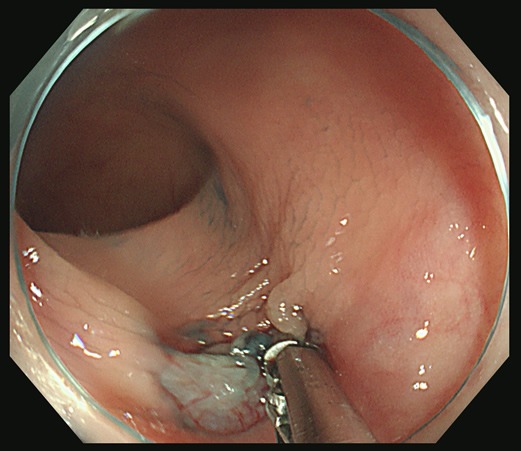

スネアー・ワイヤーを周囲の正常粘膜を巻き込みながら「広め」にかけます

十分なマージンを確保することを目指しますが、

右上方向が「ギリギリ」であることが解ります

カンシで右上方向を追加切除します